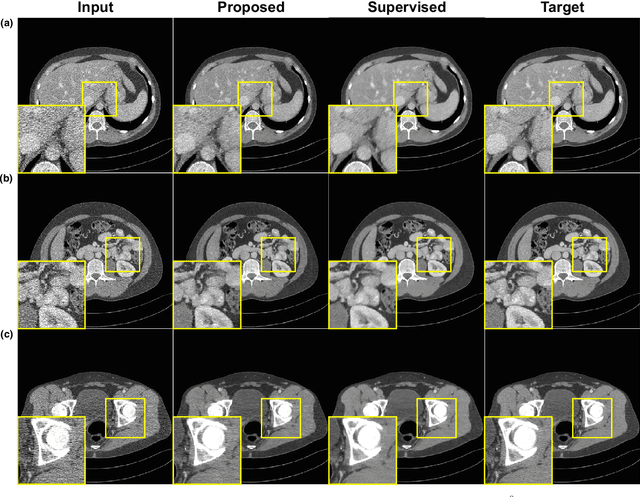

Abstract:We propose an information-theoretic knowledge distillation approach for the compression of generative adversarial networks, which aims to maximize the mutual information between teacher and student networks via a variational optimization based on an energy-based model. Because the direct computation of the mutual information in continuous domains is intractable, our approach alternatively optimizes the student network by maximizing the variational lower bound of the mutual information. To achieve a tight lower bound, we introduce an energy-based model relying on a deep neural network to represent a flexible variational distribution that deals with high-dimensional images and consider spatial dependencies between pixels, effectively. Since the proposed method is a generic optimization algorithm, it can be conveniently incorporated into arbitrary generative adversarial networks and even dense prediction networks, e.g., image enhancement models. We demonstrate that the proposed algorithm achieves outstanding performance in model compression of generative adversarial networks consistently when combined with several existing models.